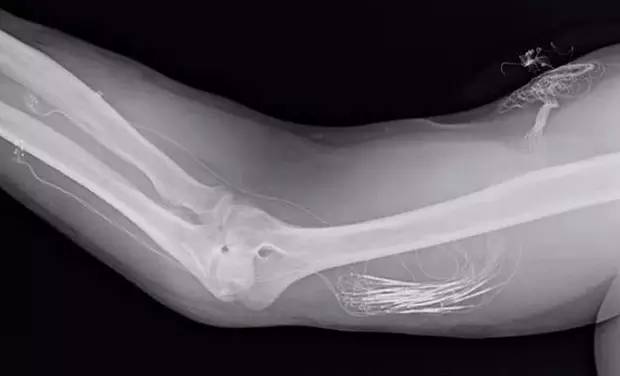

虽然听起来“植入”是很简单的,但是真正操作起来是需要志愿者做出一些牺牲的。他需要接受一场外科手术,手臂接入人造神经元电极,其中附带了电信号感应器,将其植入到人体手臂残存的神经里面后,它就扮演了连接人体神经系统和假肢微电子设备的“接口”角色。

Spetic的前臂植入了电极,上臂有导线与计算机相连

在2014年时,研究人员在Spetic的前臂植入了3个电极接口,而后较多可以达到8个,等到下一代研发出来的时候,可能会达到现在的4倍。电极接口越多,越有可能使佩戴假肢的人重获更细致的感觉。

电极接口